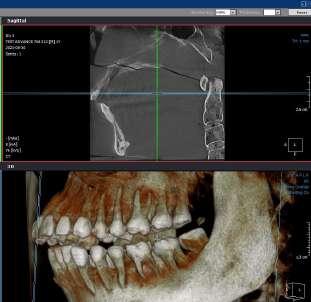

This article describes in detail how the use of a surgical kit that allows modifications made during the planning offset to be taken to surgery is a very useful tool for fully guided and accurate implant placement and digital tools to further assist in the rehabilitation.

The use of SCAIS (Static Computed Implant Surgery) has become an everyday technique in implantology practice due to its many advantages that have been well documented over the last few years.

One of the main limitations in the case of guided surgery is the planning offset, which will indicate the position of the sleeves or limit as far as our drilling should go. Being the same sleeve the one that will indicate the final position of our mounter and, consequently, of our implant. This offset will be linked to the manufacture of the drills and conveyors of our surgical kit to be used. However, in specific cases where soft tissues, teeth or the patient’s own bone do not allow us to place the sleeve deeper due to a collision with these tissues, it becomes a real limitation that in some cases restricts the final position of the implant. In some situations we can change the planning offset, and change the length of the drill as well; however, when it comes time to use the mounter to bring the implant into the final position, the mounter is usually only manufactured in a single length according to the original offset with which the system was created. This limits the restrictive guided placement of the implant significantly and the final position of the implant.

This article describes how the use of a universal surgical kit can solve this type of limitation and make the most of our guided surgery.

Dynamic Abutment Solutions has recently developed a universal guided surgery kit for placement that allows modification of the offset since the design of the guide; allowing the placement of the implants in the prosthetically planned position, thanks to the different lengths of the drills specific implant mounters.

60 year old male patient visits the clinic with the desire to restore his oral health in a fully comprehensive manner.

Upon physical examination we found absence of teeth in both jaws and remaining teeth with recurrent caries, advanced periodontal disease and mobility; with a poor prognosis for function and aesthetics. We proceeded to take all the preparatory records such as: scans, photographs, x-rays, tomography and other diagnostic elements for the planning of rehabilitation by means of dental implants.

According to the prosthetic planning in the co diagnostix software, it is decided to extract the remaining upper teeth, leaving two teeth temporarily for stabilisation of the surgical guide and as a reference for the immediate scanning after the placement of 4 single-stage implants (Fixo. Oxy. Italy).

In the lower part the extraction of the remaining teeth is planned and the immediate placement of 6 implants (dynamic hex. Cortex . Israel) and and the immediate placement of Multi Units Abutments (MUA. DAS. Dynamic Abutment Solutions. Spain). However, when planning for the lower implants at the same level, there is a collision of the sleeves with the bone that prevents the placement of the implants at the same level (fig. 6), so the offset of the anterior implants is modified to ensure the correct position in the guide, avoiding interference with the bone and placing the implants at the same level (fig. 7).